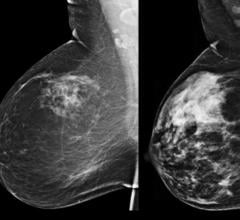

Despite decades of progress in breast imaging, one challenge continues to test even the most skilled radiologists ...

Two decades of research on the masking risk of dense breast tissue by mammography screening is indisputable. As the ...

An analysis of breast cancer data revealed that many small breast cancers have an excellent prognosis because they are ...